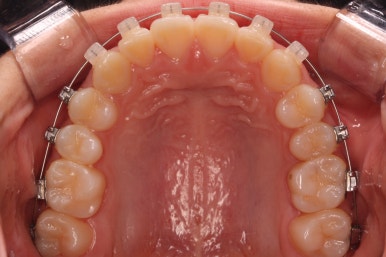

부산치아교정잘하는곳 처음 오셨을 때의 입안 모습입니다.

맨 우측 밑에 사진을 보시면 이가 하나 더 나와야 할 자리에(화살표) 앞뒤로 치아가 쓰러지면서 자리를 거의 없애버렸습니다.

따라서 이가 나올래야 나올 수가 없는 상태였습니다.

왼쪽 맨 위 사진을 보시면 아래 치열의 중앙이 한 쪽으로 쏠린 것을 알 수 있는데요. 역시 치아가 나올 자리가 없어지면서 치열이 쏠러버렸다는 것을 알 수 있습니다.

아래쪽이 더 시급하므로 브라켓 부착을 하여 가지런히 하기 시작했고 위쪽은 악궁확장장치를 입천장에 하여 위턱뼈를 가로로 넓혀주기 시작합니다.

윗니에도 이제 장치를 모두 붙였습니다. 아래쪽은 어느 정도 가지런해지고 나면 부족한 자리를 만들어주기 시작합니다.